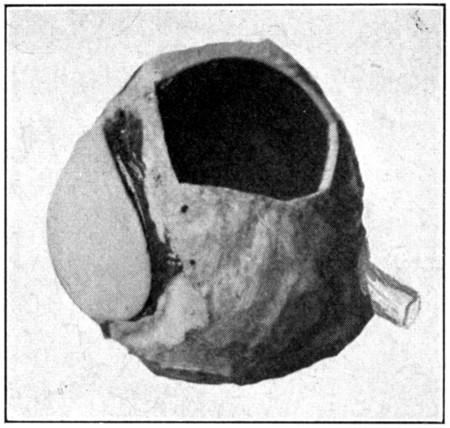

Fig. 57—Showing window cut in sclerotic, choroid, and retina.

Still another way to see the interior is to cut out a piece of the sclerotic about the size of a twenty-five-cent piece; then pinch up and tear out the choroid and the retina under the opening made in the sclerotic. (Fig. 57.) Hold the eye, the cornea forward, close to a bright light, and the image of the light will be seen upon the retina. The closer the light is to the eye, the greater the illumination will be in the[111] interior of the eye. If the opening or “window” is close enough to the optic nerve, the optic papilla can be seen easily. And, if care has been taken to have the opening made midway between the two branches of the retinal artery, the entire course may be followed. The direction of the retinal artery can be determined by ophthalmoscopic examination.